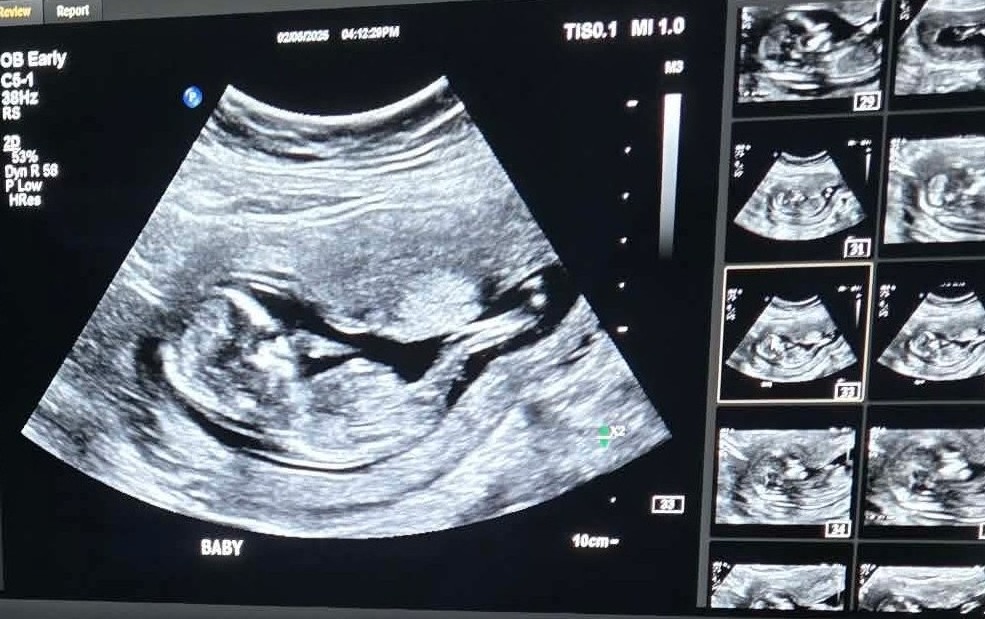

We are incredibly excited to share that another bundle of Marjoy is on the way, arriving August 2026!

Our promise is that we raise Ernie and his future sister (mic drop – we’re gonna be girl dads!) to be humble, kind and respectful little people.